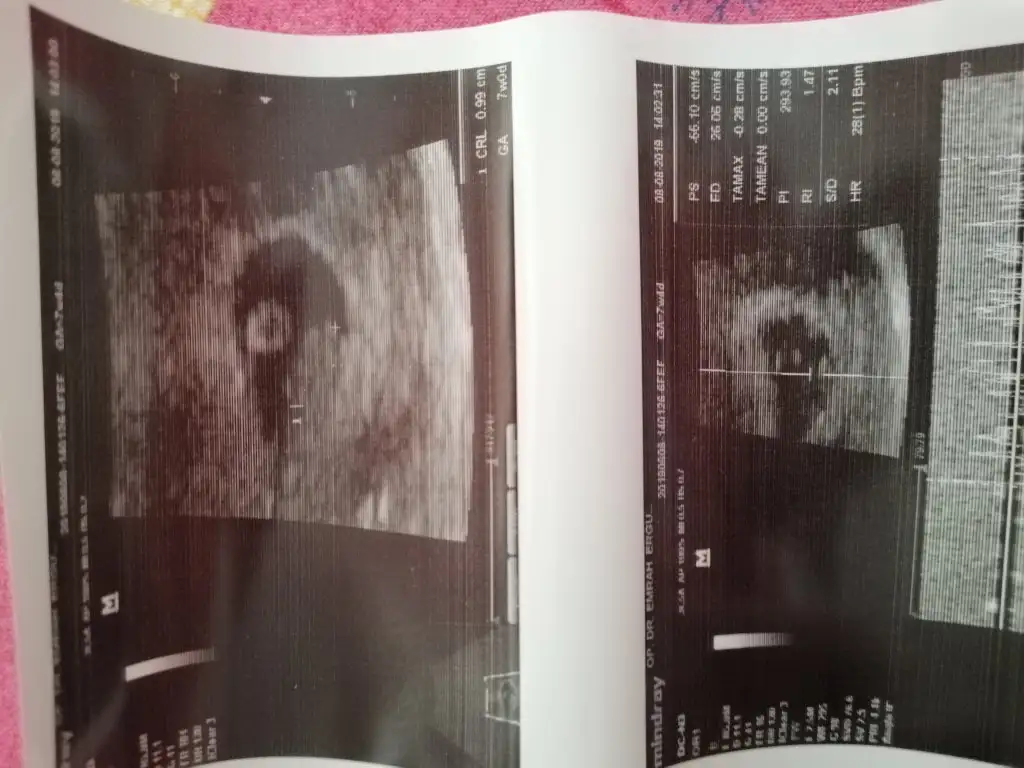

Masallah canimm kol cikintilari falan nasil belliTsk ederim canim bu doktora göre tam 9du 1 gun fazla çıktı canimdisardayim da cekmem zaman aldi

Ediyorum Canim etmem mi hiç inşallah hepiniz görürsünüz bu guzel manzarayıMasallah canimm kol cikintilari falan nasil belliayyy dua et darisi basimiza hepimizin ben de bayramdan sonra gideceğim insallah. Guya 12.haftayi bekleyecektim